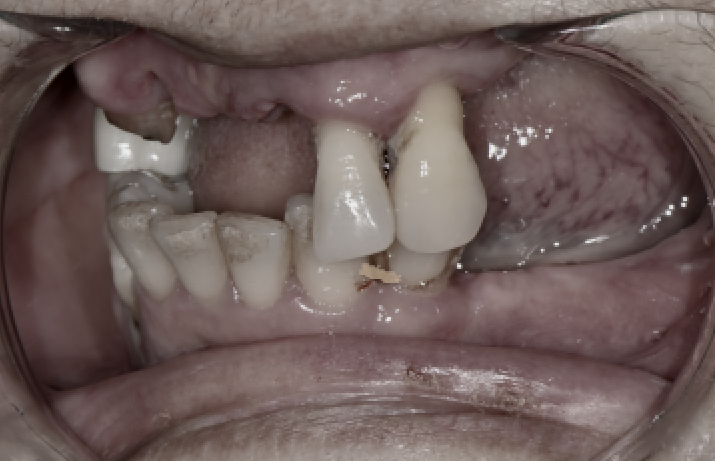

Condition at the first visit

Before full-mouth implants

The patient had weakened teeth in several areas, including the front teeth and molars,

and the remaining teeth were also loose or broken,

so they were barely functioning.

In particular, many molar areas were already missing teeth,

making it difficult to eat anything other than soft foods.